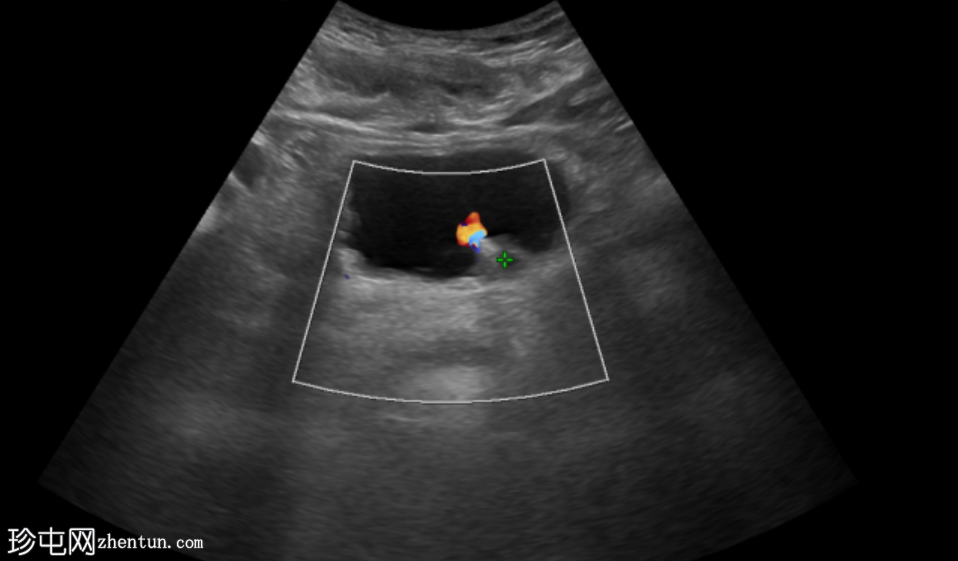

超声

检查

超声显示左侧轻度肾积水,由膀胱输尿管连接处一枚7毫米的远端输尿管结石阻塞所致,输尿管射流正常。